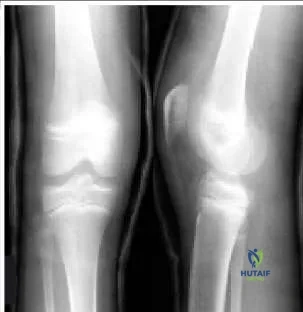

Question 6

An 8-year-old boy was injured by a lawnmower. The resulting proximal tibial injury presented in the radiograph (Slide) is classified as a:

Orthopedic Prometric Exam Chapter 3 Image

Explanation

A Salter IV injury to the proximal tibia is apparent in the patientâ s radiograph. The fracture traverses the epiphysis, physis, and metaphysis medial to the tibial spine. No injury to the lateral portion of the plateau is present. Incidentally, the distal femoral injury is also classified as Salter IV.